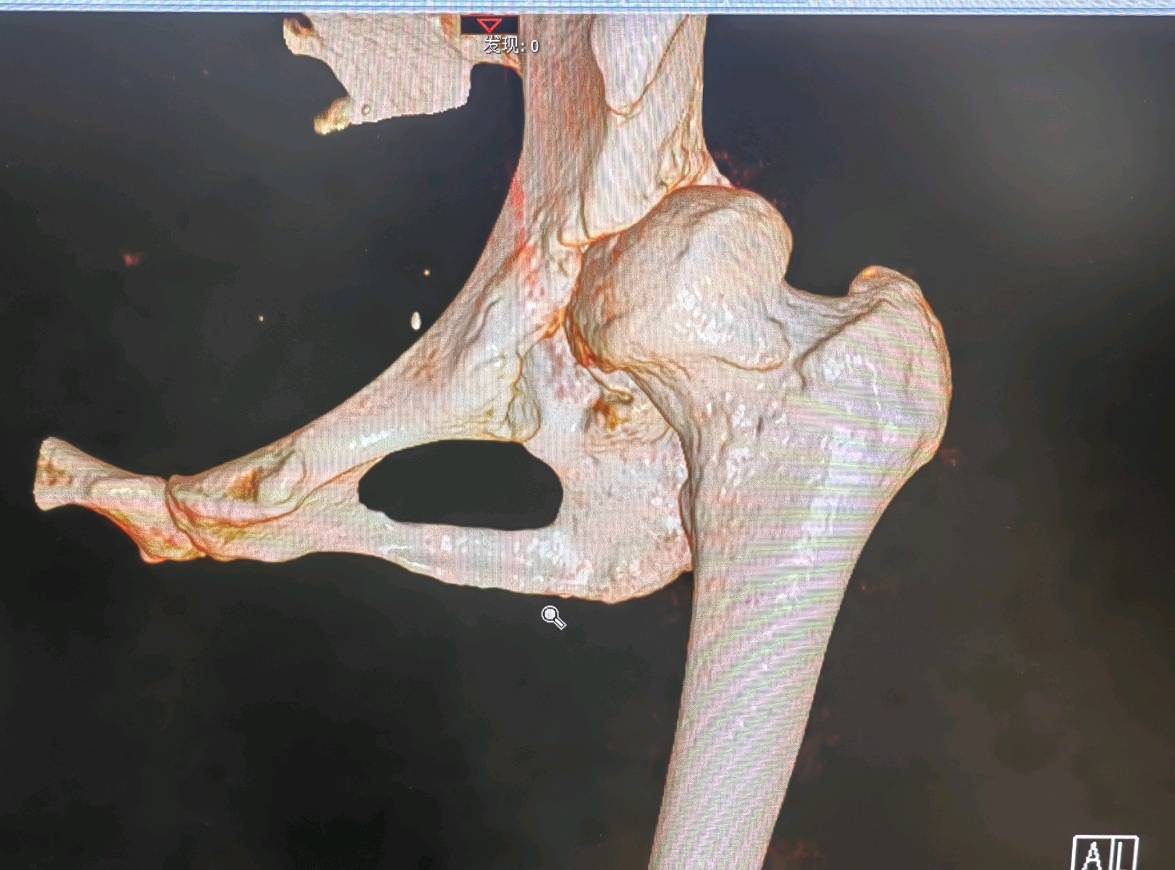

X光片、CT或MRI等影像学检查为手术决策提供了客观依据。当出现以下表现时,说明关节软骨已经严重磨损,退行性变已进入晚期:

1. 关节间隙显著狭窄或消失:这是软骨几乎完全磨光的直接证据,导致骨头与骨头直接摩擦(“骨对骨”)。

2. 出现大量骨赘(骨刺):关节为增加稳定性而代偿性增生,但会加剧疼痛和僵硬。

3. 软骨下骨硬化或囊性变:骨头因长期异常受力而变得致密(硬化)或出现囊性空洞,这常常是疼痛的来源之一。

4. 继发性骨关节炎:髋臼发育不良的最终结果就是导致髋关节过早地出现严重的骨关节炎。